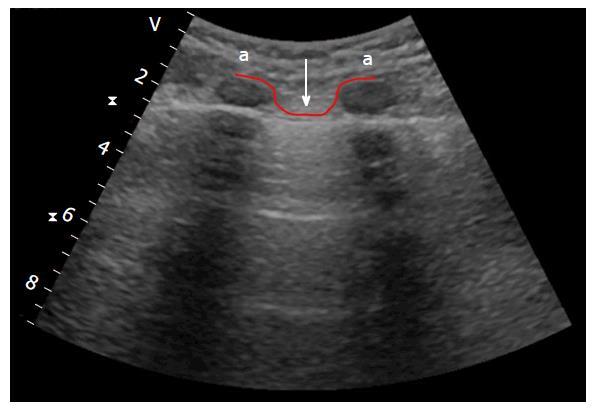

What is the “bat sign” in lung ultrasound?

Image formed by two ribbs with the pleural line in between them = resembles a bat with open wings.